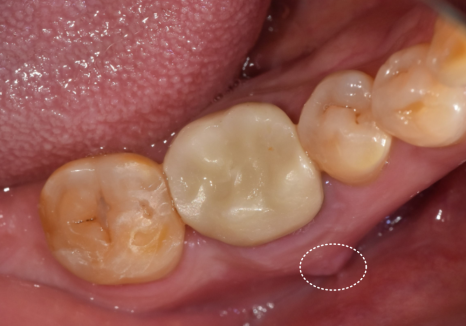

우선 발치 후 주변에 퍼진

염증을 깨끗하게 긁어내고,

부족한 뼈를 보강하기 위해 뼈이식과 함께

임플란트 뿌리를 정확한 위치에 식립해 드렸습니다.

식립 후 3개월 뒤,

뼈가 확실히 굳은 것을 확인하고

정밀 스캐너로 본을 떠서

최종 지르코니아 보철을 완성해 드렸습니다.

주변 치아와 조화를 이루며

자연스럽게 마무리된 모습입니다.^^